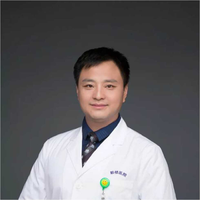

乳腺黏液性囊腺瘤伴导管内癌